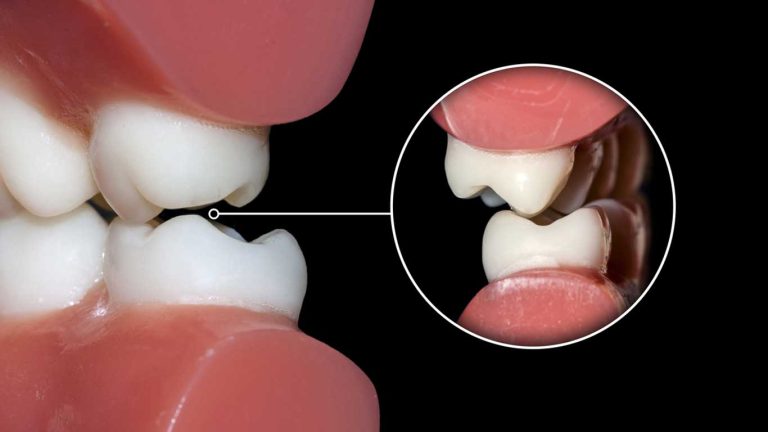

- ایجاد بایت ایده آل: روابط بین دندان های فک بالا و پایین باید به یک حالت پایدار و عملکردی رسیده باشد.

ابتدا، متخصص ارتودنسی با استفاده از یک انبرک مخصوص، هر براکت را به آرامی از روی سطح دندان جدا می کند. این کار با اعمال یک فشار کنترل شده انجام می شود که پیوند بین چسب و براکت را می شکند. سپس، باقی مانده چسب (رزین کامپوزیت) که روی سطح دندان ها باقی مانده است، با استفاده از یک هندپیس و فرز های پرداخت بسیار نرم و بدون آسیب رساندن به مینای دندان، تراشیده و پاک می شود. در نهایت، سطح تمام دندان ها با استفاده از خمیر ها و برس های مخصوص پولیش داده می شود تا هرگونه لکه سطحی از بین رفته و دندان ها ظاهری صاف و درخشان پیدا کنند.

ظاهر دندان ها | پوشیده شده با براکت و سیم های فلزی یا سرامیکی | صاف، مرتب، درخشان و کاملا نمایان |

احساس در دهان | احساس وجود جسم خارجی، گاهی زبری و تیزی | احساس صافی و نرمی غیر منتظره روی سطح دندان ها |